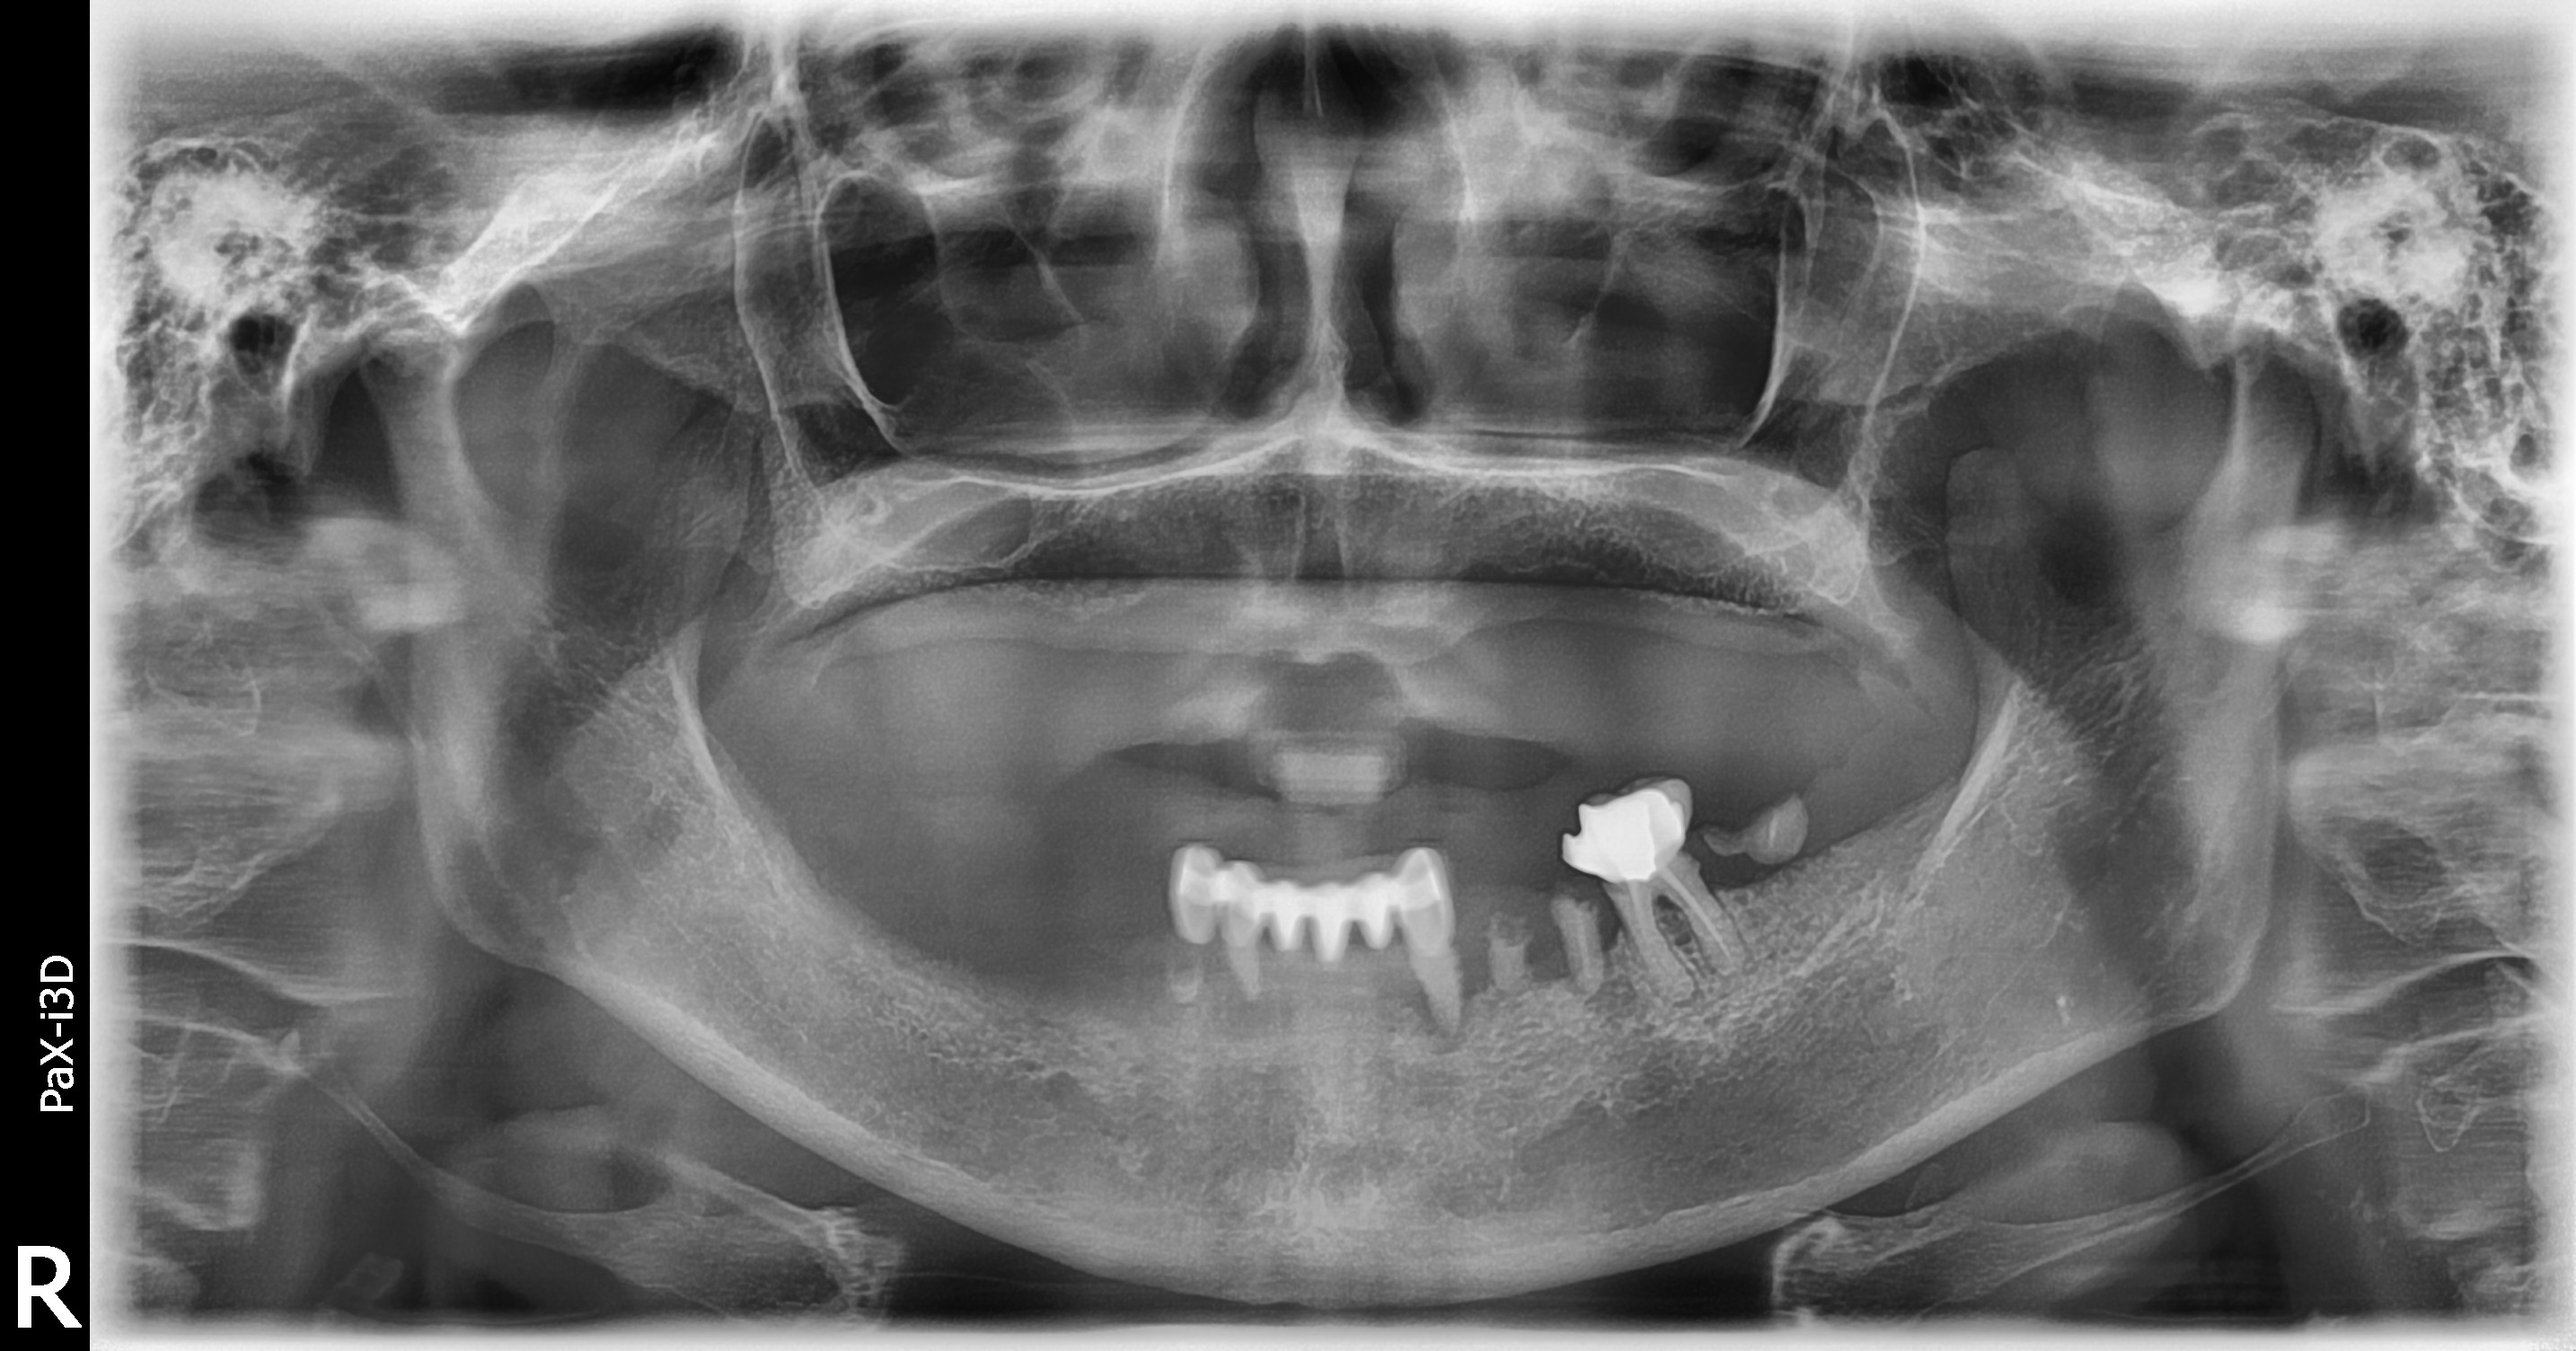

임플란트/틀니

임플란트 틀니

부분틀니

전체틀니/부분틀니

상악동 거상술